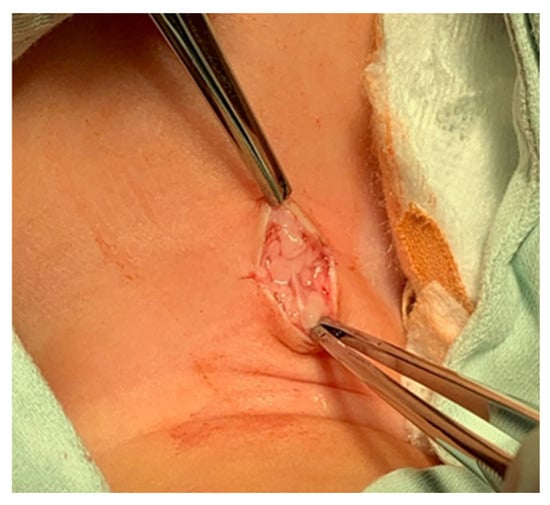

- The subcutaneous tissue is carefully dissected (Figure 2).